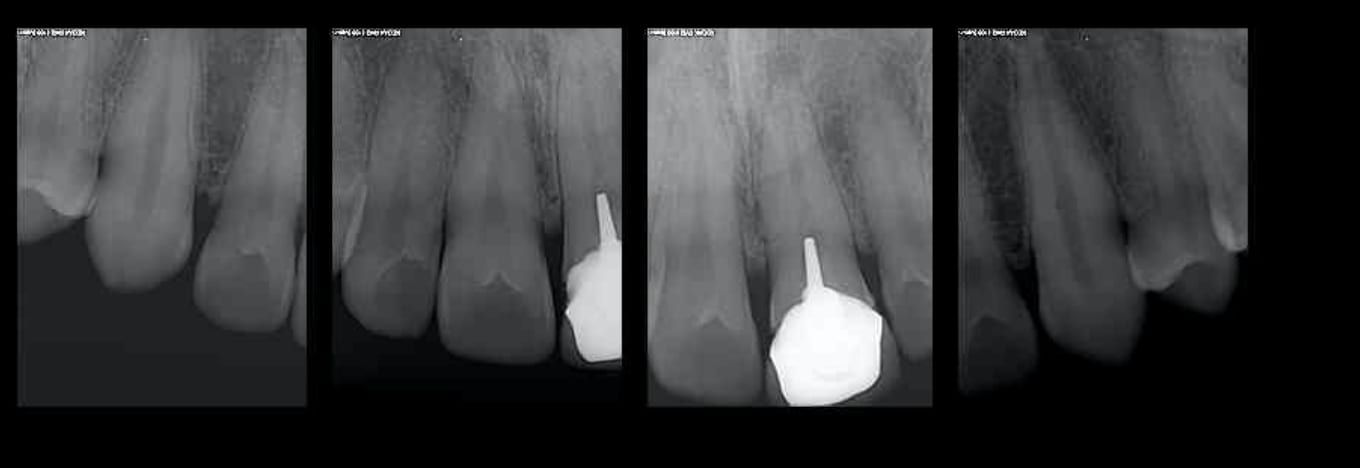

Pour commencer, Junior, est ce que toutes tes endos sont à l'apex et faites sous digue ? Pour grimper à un arbre il faut s'assurer d'abord qu'on a le cul propre. Il s'agit surtout de fraude à la qualité qui est la plus fréquente, c'est un constat de tous les jours. Pour ce qui est de la fraude à la sécu, c'est l'arroseur arrosé, un assureur en situation de monopole qui baisse ses remboursements et les transfère aux mutuelles, elles mêmes obligatoires, qui augmentent leurs cotisations c'est du racket en bande organisée.

Pour répondre à ta remarque Chicot29, je n’ai pas de scrupule, je pense mettre tout en œuvre pour que les soins soient conformes aux données actuelles. Je ne suis pas inquiet pour cela.